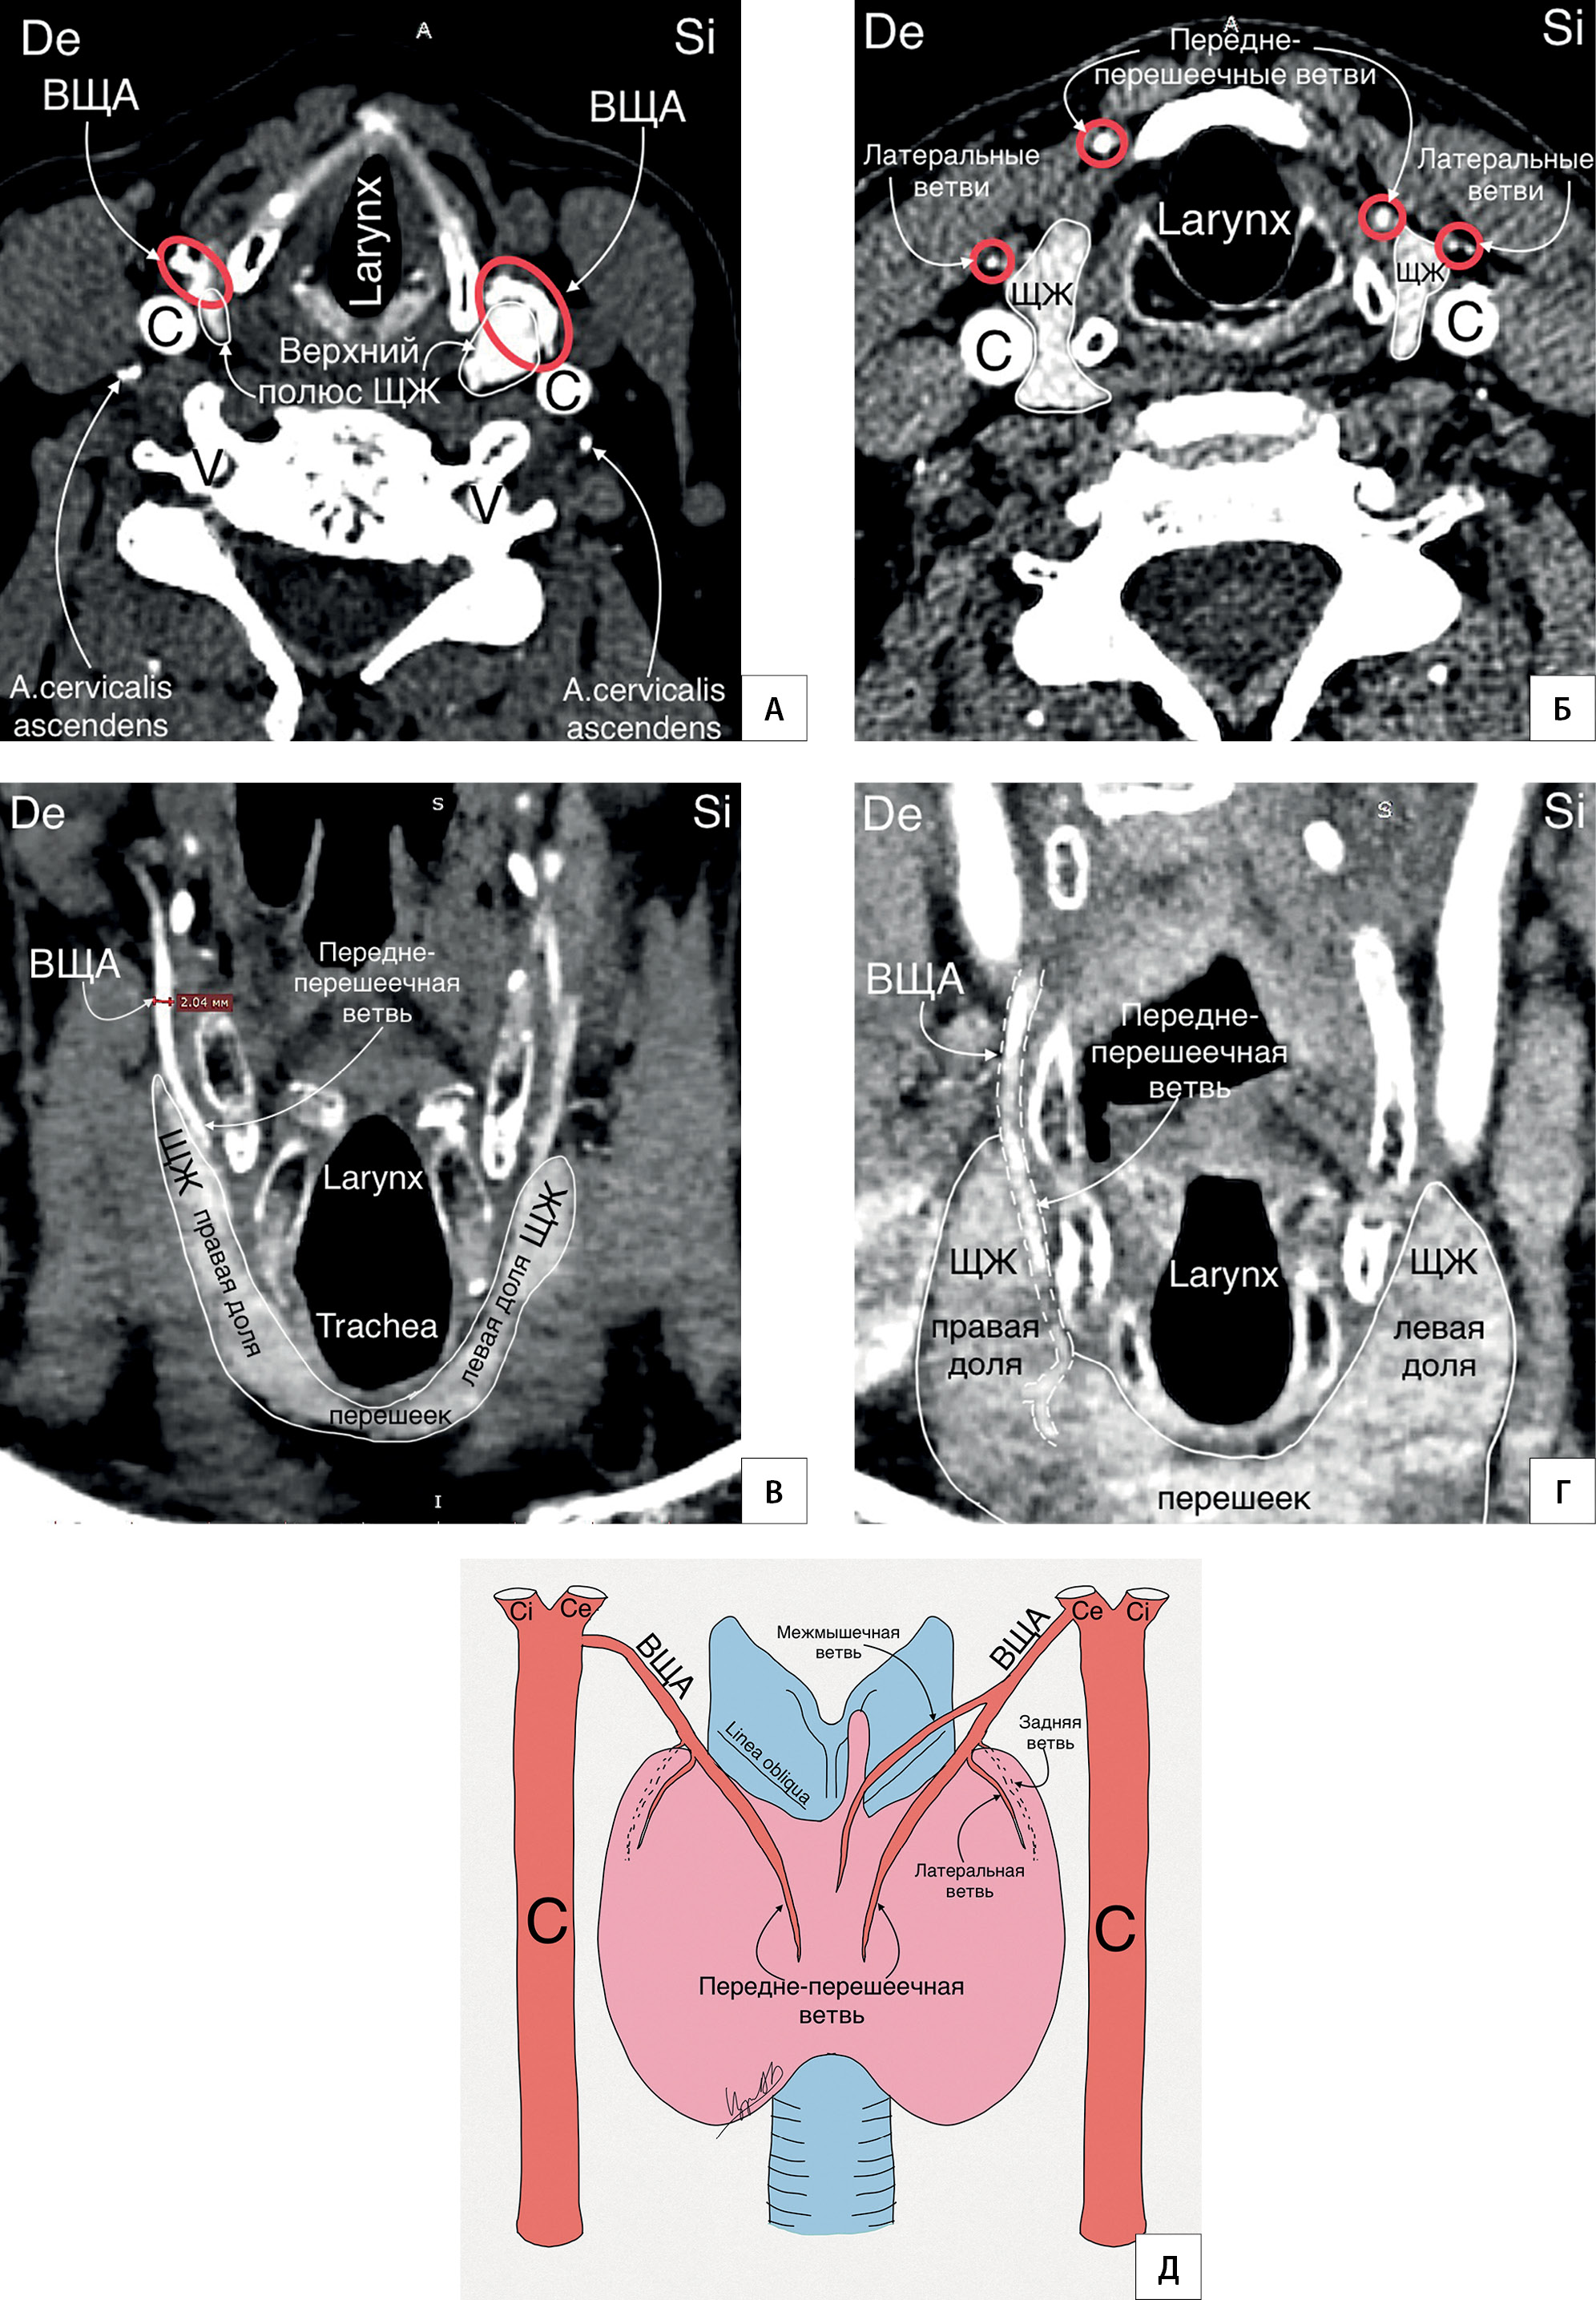

12. Рисунок 12. Расположение железистых ветвей ВЩА. А — КТ-ангиография (горизонтальный срез на уровне верхних полюсов ЩЖ); Б — КТ- ангиография (горизонтальный срез несколько ниже рисунка А); В, Г — КТ-ангиография (фронтальный срез на уровне перешейка ЩЖ); Д — схематичный рисунок. Передне-перешеечная железистая ветвь является самой постоянной и крупной железистой ветвью ВЩА. Linea obliqua (TA) — косая линия щитовидного хряща — место крепления прещитовидных мышц; C — a. carotis communis; Ce — a. carotis externa, Ci — a. Carotis interna; V — a. vertebralis; De — dextra, Si — sinistra.

Тема

Тип Исследовательские инструменты

Посмотреть (822KB)

Метаданные ▾